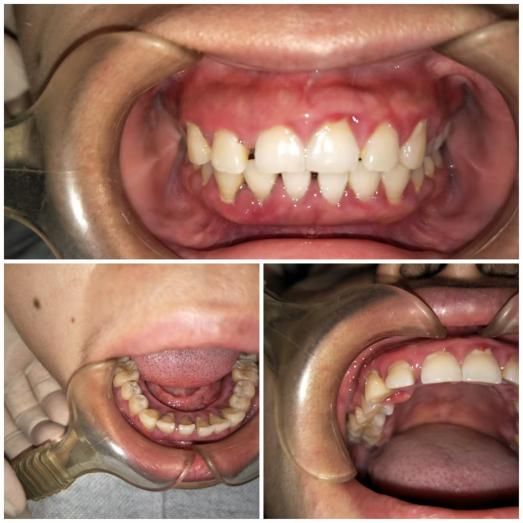

这天,涪陵区人民医院口腔科来了一位40岁的女性患者,她焦急地对医生说:“我刷牙出血有4年多了,吃饭出血、吃水果出血,刷牙更是出血多。这段时间更严重了,出现了不吃东西、未刷牙也出血的情况,严重影响我的工作和生活,医生,我是不是得了什么绝症啊?”经过医生仔细询问病史,开展口腔内检查,同时进行生命体征监测,发现患者口腔内牙龈明显红肿,轻轻触碰即可见鲜血溢出,见牙齿表面及牙龈深部覆盖大量牙结石、软垢,口臭明显。

通过对患者进行口腔全景片检查及全身系统性疾病(血源性疾病、肝功能异常及糖尿病病史等)排除后,口腔科诊断为:慢性牙周炎(中度),并制定针对性的治疗计划:序列牙周治疗。通过2次完善超声龈上洁治+超声、手工龈下刮治+手工根面平整等系列牙周基础治疗,1个月后患者的牙龈健康得到明显改善,牙龈不再出血,口臭也明显减轻。